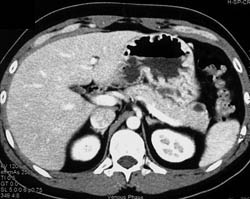

Hepatic Artery Aneurysm